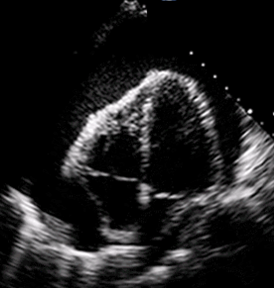

Our Fellowship is based on the current EUFAC guidelines and additional requirements that are specific to our institution. The RUHS, Emergency Department is a busy, high-acuity Level 1 Trauma Center, and Pediatric Trauma Center with an annual census of more than 95,346 patients. The RUHS ultrasound program has a unique focus integrating POCUS into resuscitation including advanced hemodynamic instruction and resuscitative transesophageal echocardiography.

- Our department has fully integrated advanced hemodynamic POCUS into all our resuscitations, including resuscitative transesophageal echocardiography.

TTE

TEE